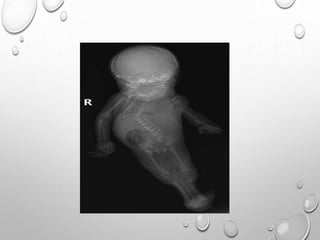

THANATOPHORIC DYSPLASIA

MOST COMMON LETHAL SKELETAL DYSPALSIA.

PREVALENCE 0.24 TO 0.69 PER 10000 BIRTHS.

TWO TYPES….

TYPE 1 – TELEPHONE RECEIVER EXTREMITIES

BUT WITHOUT CLOVERLEAF SKULL.

TYPE 2 – CLOVERLEAF SKULL

WITHOUT TELEPHONE RECEIVER

EXTREMITIES

CLOVERLEAF SKULL DUE TO

PREMATURE CRANIOSYNOSTOSIS OF THE

LAMBDOID AND CORONAL SUTURES

MACROCRANIA

FRONTAL BOSSING

FLATTENED NASAL BRIDGE WITH MID FACE HYPPLASIA

DECREASED THORACIC CIRCUMFERANCE

NORMAL TRUNK LENGTH

SEVERE MICROMELIA ….RHIZOMELIC TYPE

TELEPHONE RECEIVER EXTREMITIES….BOWED , CURVED

APPEARANCE SECONDARY TO BROADENED METAPHYSES

PLATYSPONDYLY

WAFER THIN VERTEBRAL BODY WITH RELATIVELY LARGER

HYPOECHOIC DISC SPACE .

CNS FINDINGS….HOLOPROSENCHEPHALY , AGENESIS OF CORPUS

CALLOSUM ,HETEROPTROPIA , POLYMICROGYRIA ,

VENTRICULOMEGALY

MINERALIZATION IS NORMAL